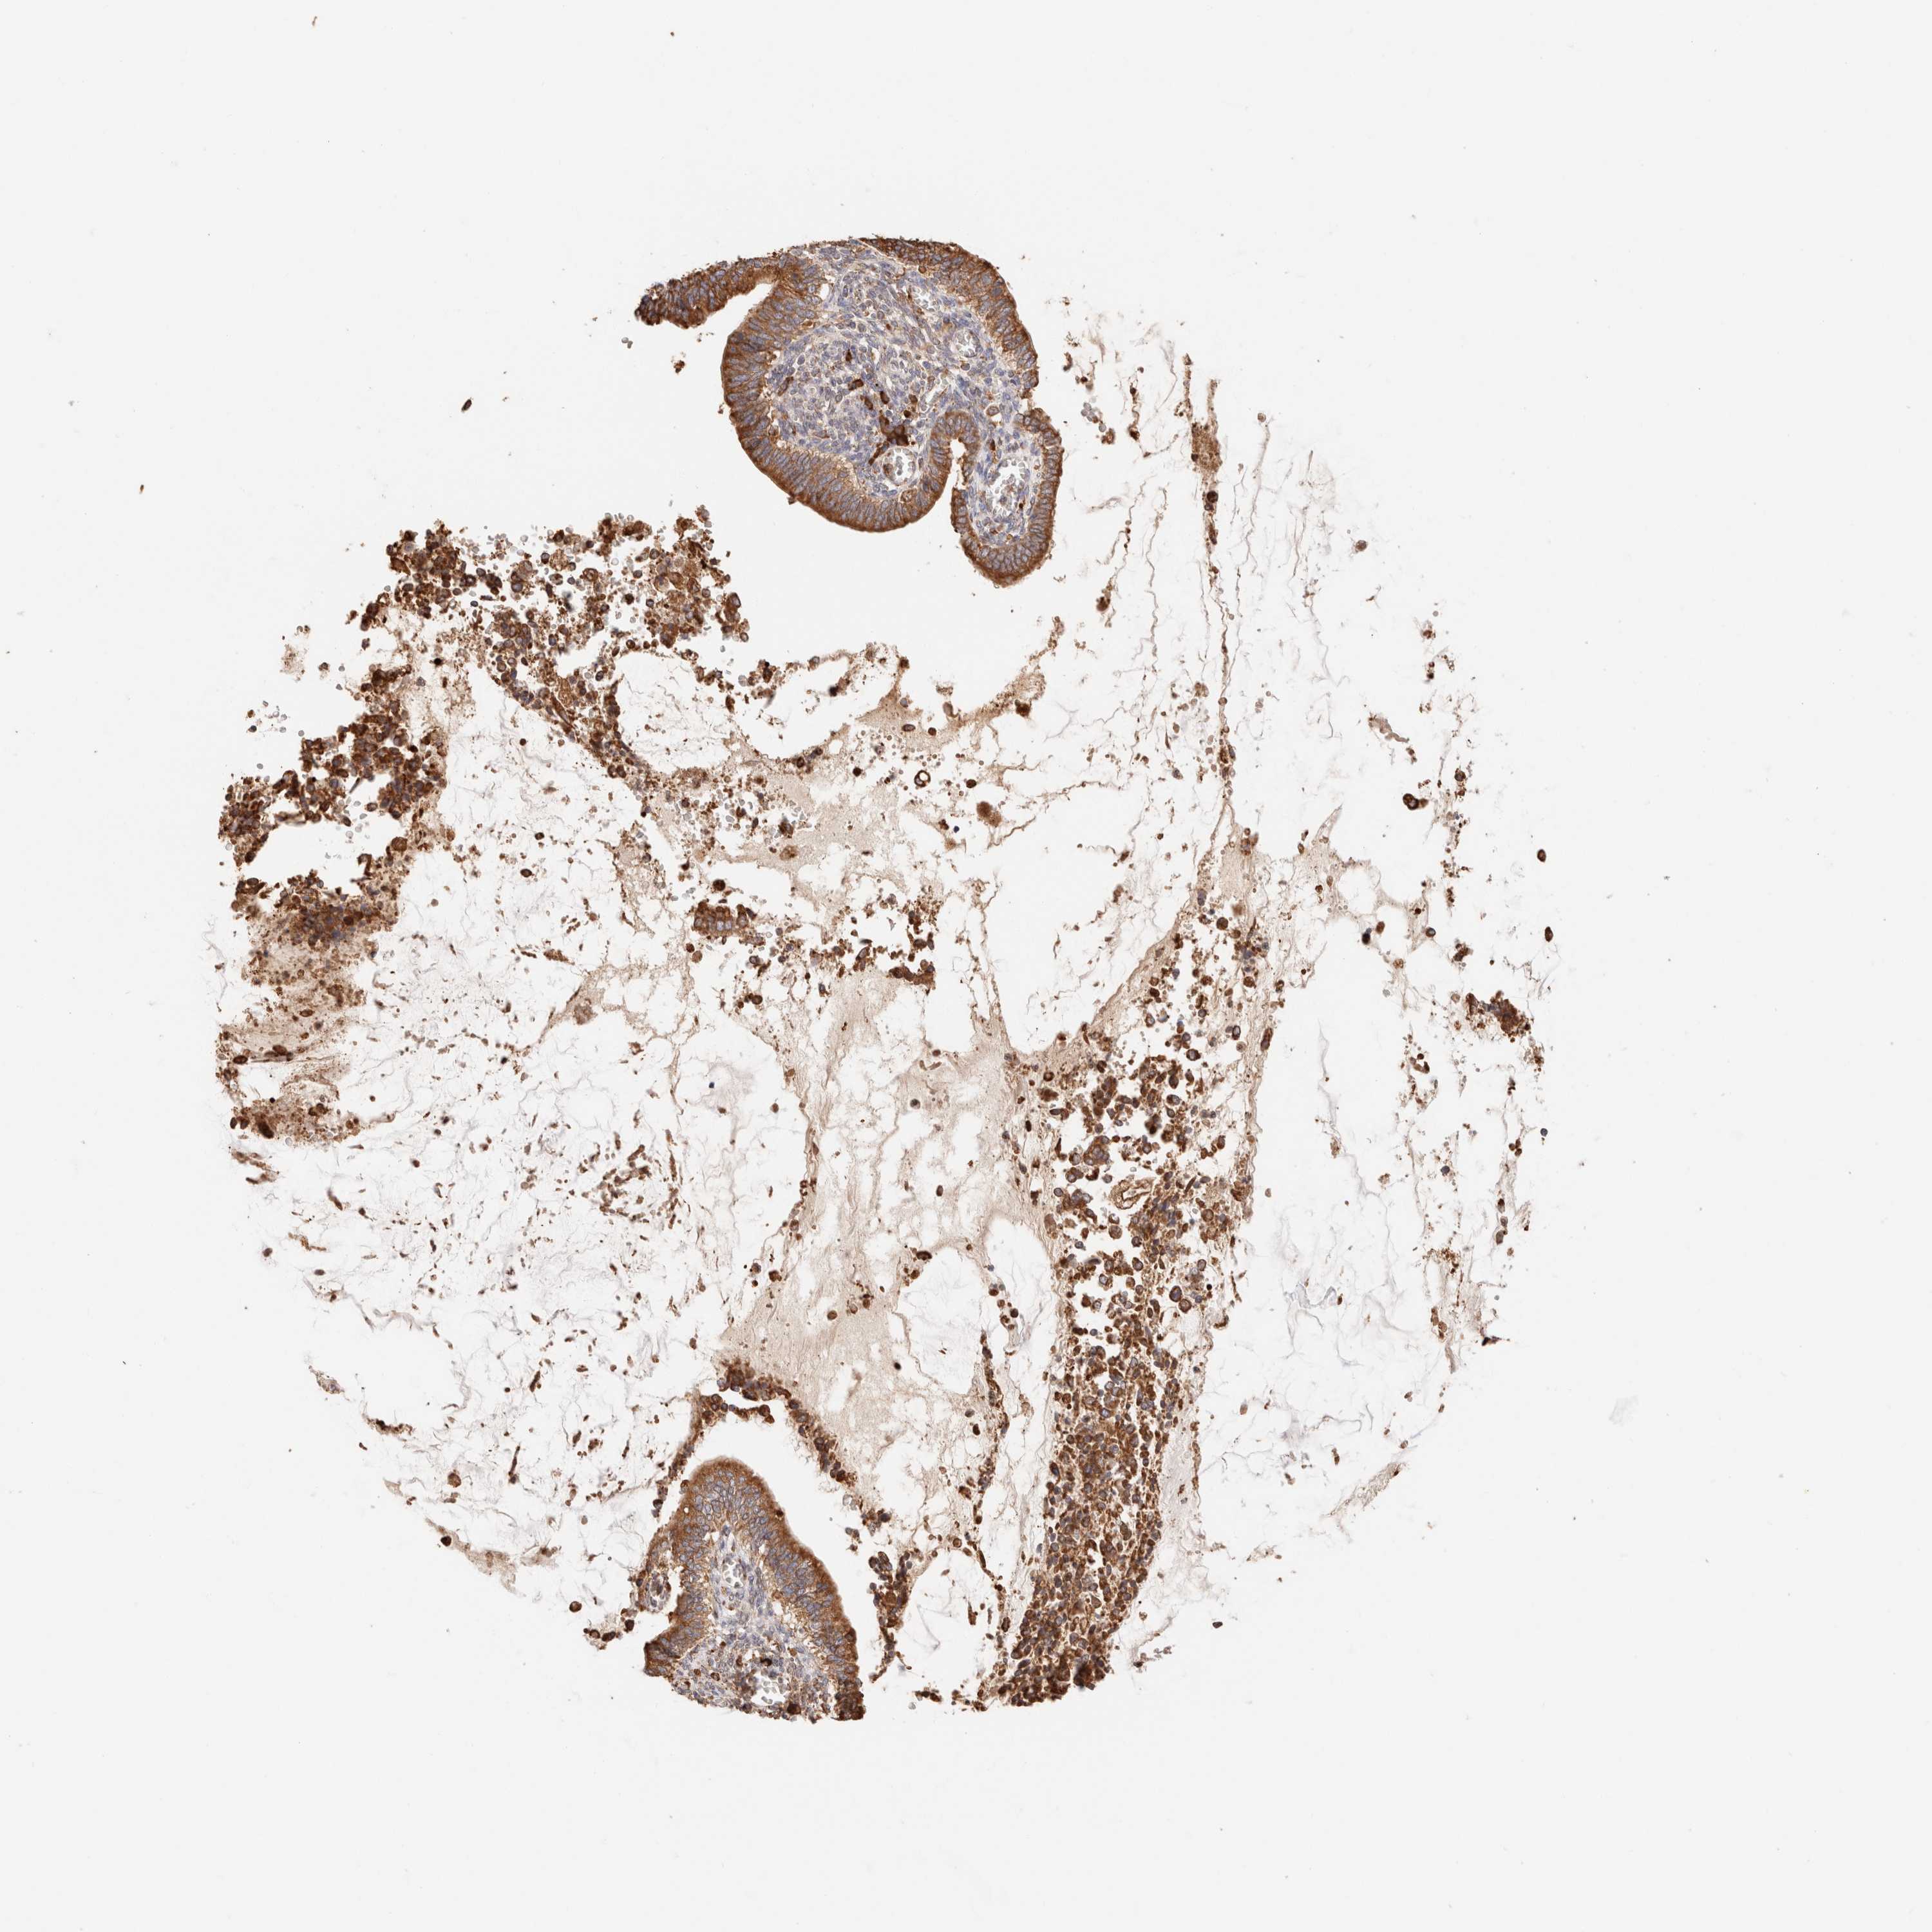

CERVICAL CANCER - Protein expressioni

A mouse-over function shows sample information and annotation data. Click on an image to view it in a full screen mode. Samples can be filtered based on level of antibody staining by selecting one or several of the following categories: high, medium, low and not detected. The assay and annotation is described here.

Note that samples used for immunohistochemistry by the Human Protein Atlas do not correspond to samples in the TCGA dataset.

Antibody stainingi

Antibody staining in the annotated cell types in the current human tissue is reported as not detected, low, medium, or high, based on conventional immunohistochemistry profiling in selected tissues. This score is based on the combination of the staining intensity and fraction of stained cells.

Each image is clickable and will lead to virtual microscopy that enables deeper exploration of all samples and also displays staining intensity scores, fraction scores and subcellular localization as well as patient and tissue information for each sample.

Antibody HPA007641

Antibody CAB022464

Staining

High

Medium

Low

Not detected

Intensity

Strong

Moderate

Weak

Negative

Quantity

>75%

75%-25%

<25%

None

Location

Nuclear

Cytoplasmic/membranous

Cytoplasmic/membranous,nuclear

Squamous cell carcinoma, NOS

Adenocarcinoma, NOS